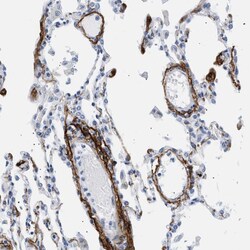

Invitrogen™ Elastin Polyclonal Antibody

Rabbit Polyclonal Antibody

Immunogen sequence: VKPGKVPGVG LPGVYPGGVL PGARFPGVGV LPGVPTGAGV KPKAPGVGGA FAGIPGVGPF GGPQPGVPLG YPIKAPKLPG GYGLPYTTGK LPYGYGPGGV AGAAGKAGYP TGTGVGPQAA AAAAAKAAAK FGAGA Highest antigen sequence identity to the following orthologs: Mouse - 85%, Rat - 83%.

This gene encodes a protein that is one of the two components of elastic fibers. The encoded protein is rich in hydrophobic amino acids such as glycine and proline, which form mobile hydrophobic regions bounded by crosslinks between lysine residues. Deletions and mutations in this gene are associated with supravalvular aortic stenosis (SVAS) and autosomal dominant cutis laxa. Multiple transcript variants encoding different isoforms have been found for this gene.

Immunohistochemistry (Paraffin)